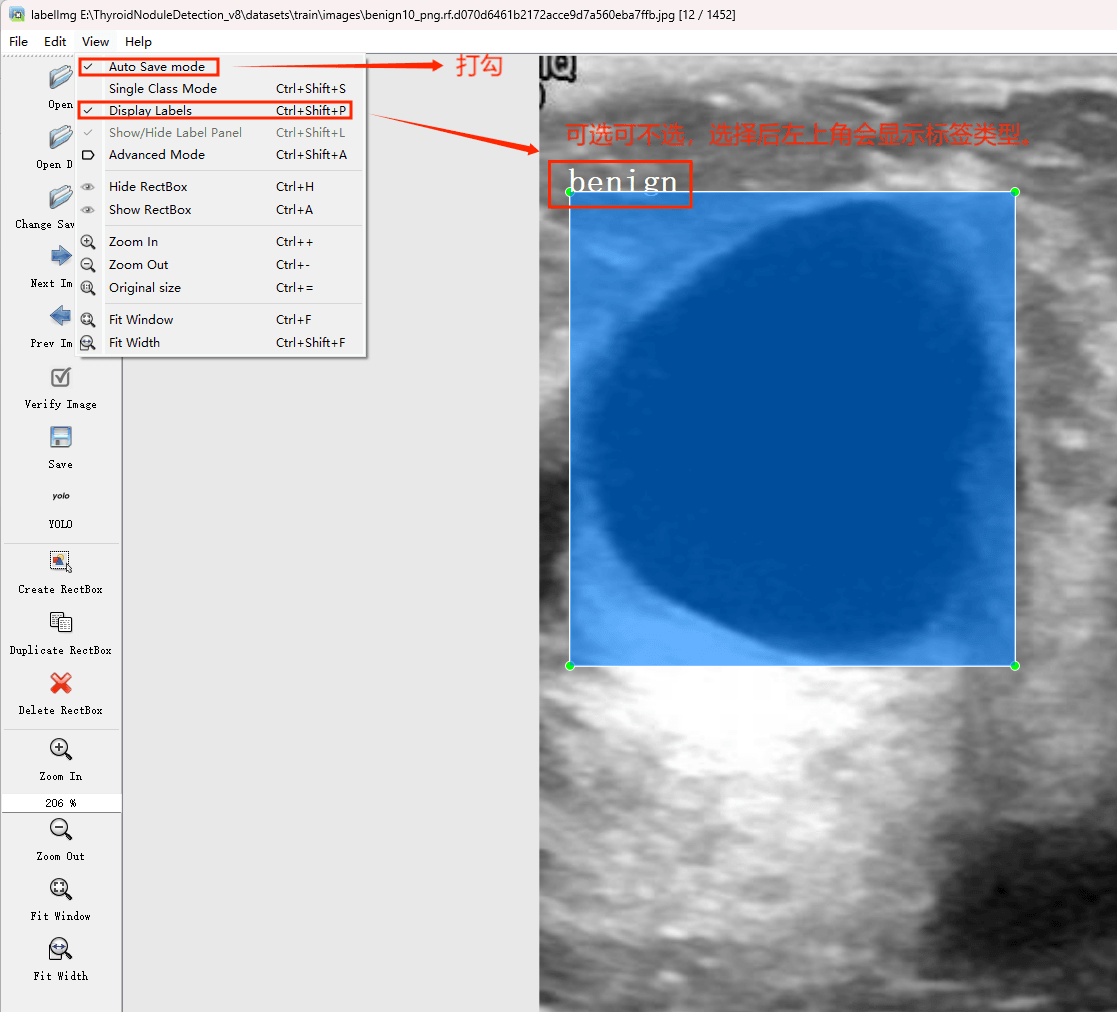

初识labelimg

打开后,我们自己设置一下

在View中勾选Auto Save mode

接下来我们打开需要标注的图片文件夹

并设置标注文件保存的目录(上图中的Change Save Dir)

接下来就开始标注,画框,标记目标的label,然后d切换到下一张继续标注,不断重复重复。